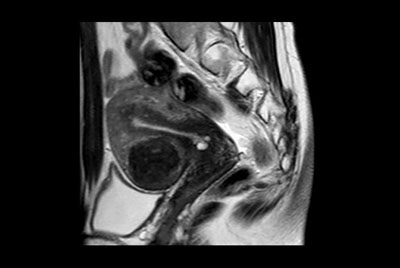

Pelvis with fistula